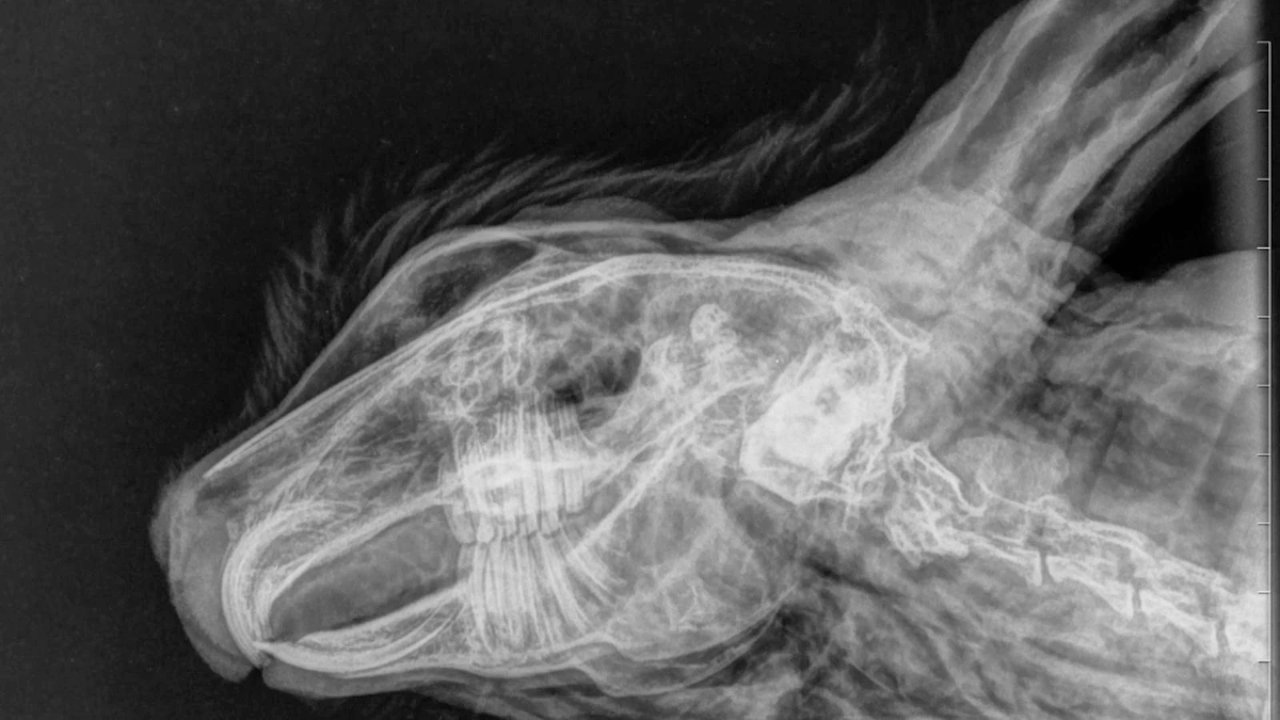

Hamburger Abendblatt:  Totes Kaninchen: Röntgen-Bilder beweisen „massive Gewalteinwirkung“